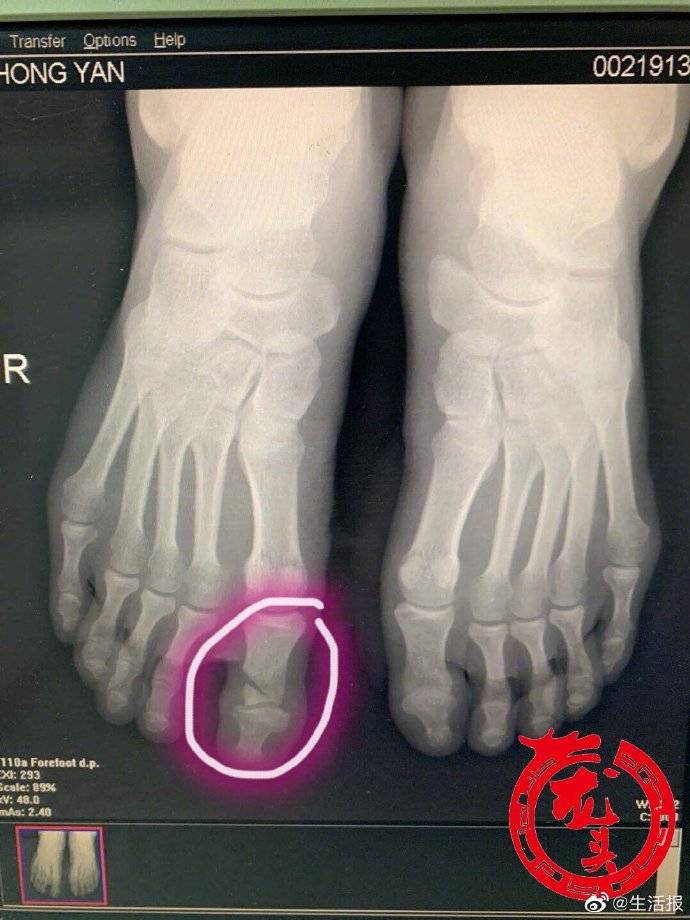

【嫌家中板凳不平男子拿起电锯 , 脚下一滑悲剧了】嫌家中板凳不平 , 男子临时当起了“木匠” , 不料脚下一滑 , 电锯从手中脱落 , 砸伤两个脚趾 , 还把其中一个脚趾砸骨折了 。 近日 , 哈尔滨市民张先生(化姓)在家中本想勤快一把 , 没成想突遭意外 , 后悔不迭 。几天前 , 张先生发现家中新买的板凳坐着有点不平 , 找人帮忙有点麻烦 , 家里正好有电锯 , 平时没事就爱修修补补的张先生自己当起了临时“木匠” 。 没想到当天张先生穿的是拖鞋 , 加上地面上有些潮湿 , 单腿着地的他一个没站稳 , 摔倒的时候 , 手中的电锯正好砸到了右脚上 , 锋利的刀刃将大拇脚指割伤 , 顿时血流如注 , 张先生疼得满头大汗 。 家人见状 , 急忙把他送到了哈医大一院急诊科 。 当时正在缓冲区值班的骨一科副主任耿硕检查发现 , 患者为电锯开放伤 , 大拇脚指骨折 , 血管、肌腱均被割断 , 紧急做了急诊清创手术 。